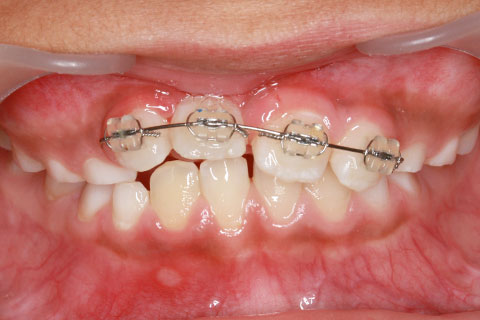

子供の乳歯が抜けて、かなりの時間が経つのに永久歯が生えてこないと心配して来院される親御様は多くいらっしゃいます。この場合、レントゲンにて確認すると大体の場合、もうしばらく待っていれば生えてくるであろうと予測がつきます。しかし、稀に歯の位置異常により、埋まったままの状態で生えてこないことがあります。この場合、待っていても生えてきませんので、矯正力により歯を引っ張り出す必要があります。これを矯正学では開窓・牽引術と呼び、歯肉を切開して、歯の表面を露出させ、そこに矯正器具を付けて、良好な位置まで引っ張り出すという治療法です。